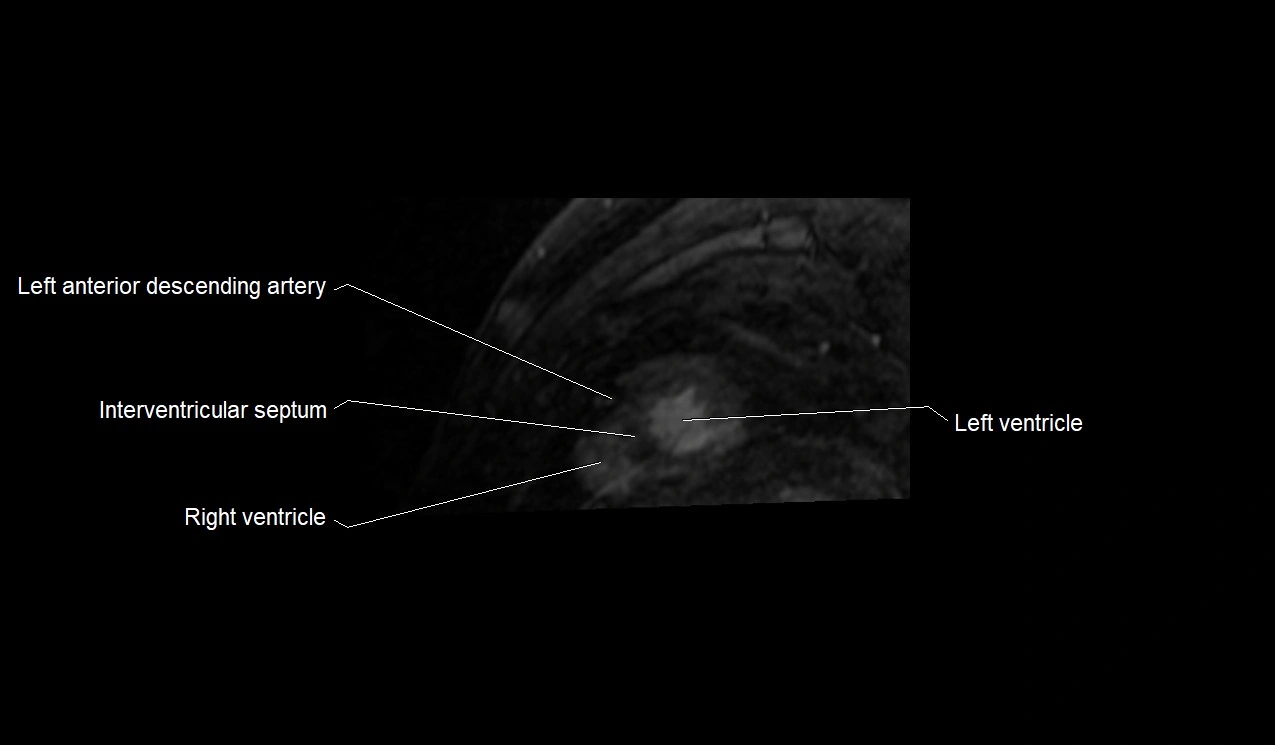

MRI image